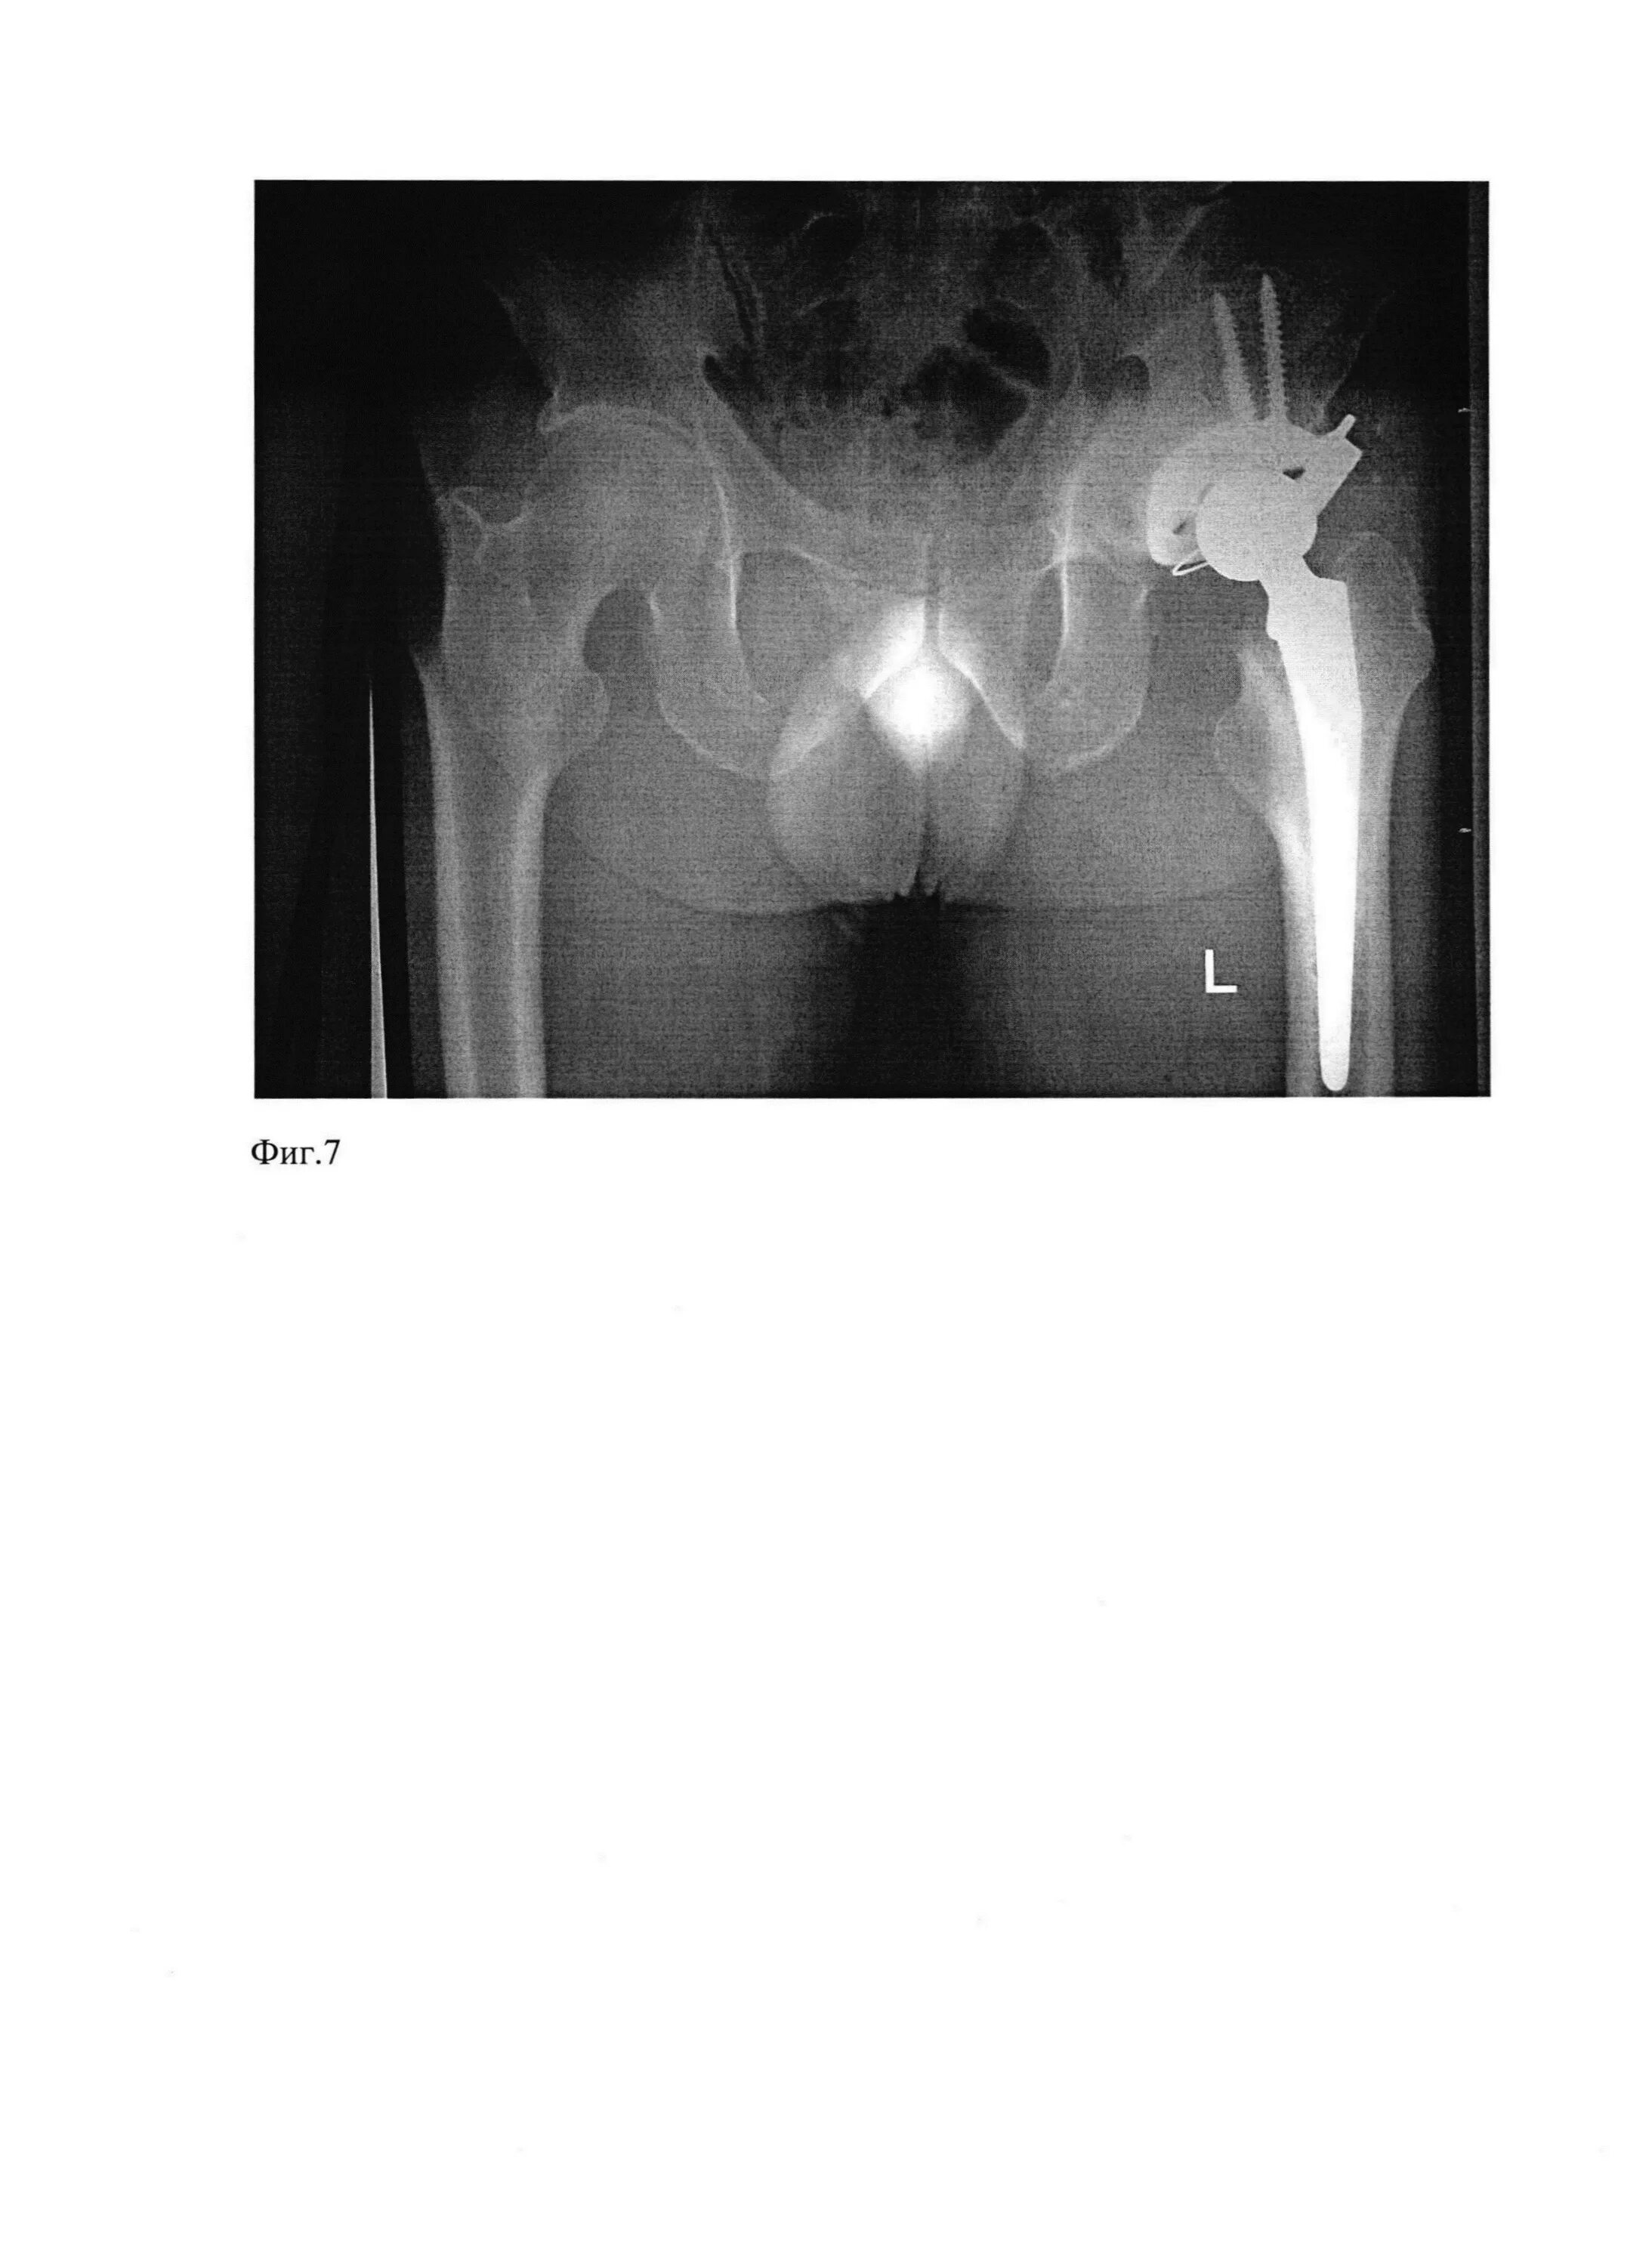

Перелом тазобедренной впадины